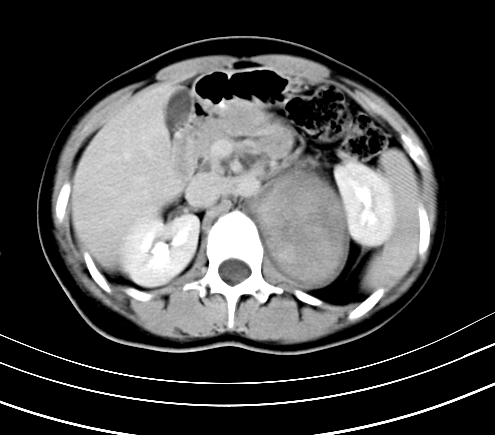

动脉期